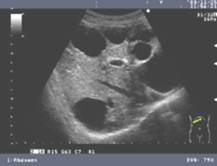

Polycistic Liver diease

Multiple cysts

2-3 cm cysts

1 in 500 people

asymotomatic

Also have polycistic renal disease!